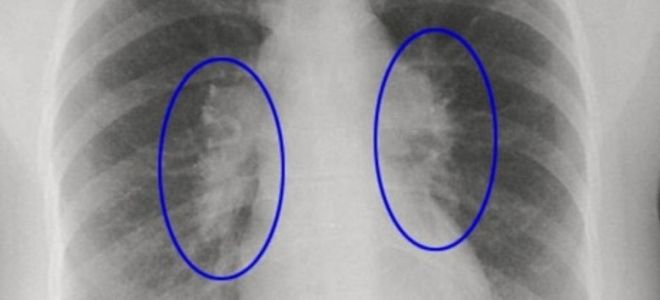

Выявление заболевания часто требует комплексного подхода, включая рентгенографию, компьютерную томографию и функциональные тесты легких. Важно отметить, что ранняя диагностика играет ключевую роль в успешном лечении.

| Как выявить фиброз легких? | 1. Сбор анамнеза и физикальный осмотр: Выявление характерных симптомов (одышка, кашель, «пальцы Гиппократа»), аускультация легких (крепитация). 2. Функциональные легочные тесты (ФЛТ): Спирометрия, бодиплетизмография, диффузионная способность легких (DLCO) – позволяют оценить объем легких и эффективность газообмена. 3. Рентгенография грудной клетки: Может выявить изменения в легких, но не всегда специфична. 4. Компьютерная томография высокого разрешения (КТВР) легких: «Золотой стандарт» диагностики, позволяет детально рассмотреть изменения в легочной ткани, определить тип и распространенность фиброза. 5. Бронхоскопия с биопсией легкого: В некоторых случаях может потребоваться для получения образца ткани для гистологического исследования и подтверждения диагноза. 6. Анализы крови: Могут выявить маркеры воспаления или аутоиммунных заболеваний, которые могут быть связаны с фиброзом. |

Современные методы диагностики: Для выявления фиброза легких используются различные методы, включая компьютерную томографию (КТ) грудной клетки, которая позволяет детально визуализировать изменения в легочной ткани. Также могут применяться функциональные тесты легких для оценки их работы и уровня кислорода в крови. Ранняя диагностика важна для начала лечения и замедления прогрессирования заболевания.

Клинические проявления этого заболевания могут напоминать симптомы других заболеваний дыхательной системы, поэтому для точной диагностики назначаются следующие исследования:

- рентгенография грудной клетки;

- компьютерная томография легких;

- магнитно-резонансная томография дыхательных путей;

- биопсия легкого;

- функциональные тесты дыхания.